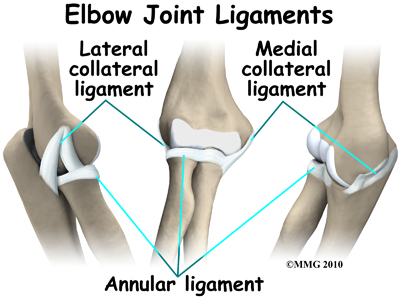

In the elbow, two of the most important ligaments are the medial collateral ligament and the lateral collateral ligament. The medial collateral is on the inside edge of the elbow, and the lateral collateral is on the outside edge. Together these two ligaments connect the humerus to the ulna and keep it tightly in place as it slides through the groove at the end of the humerus. These ligaments are the main source of stability for the elbow. They can be torn when there is a severe injury or dislocation of the elbow. These ligaments are not generally injured in the condition referred to as nursemaid's elbow.

There is also an important ligament called the annular ligament that wraps around the radial head and holds it tight against the ulna. The word annular means ring-shaped. The annular ligament forms a ring around the radial head as it holds it in place. This ligament can be torn when the entire elbow or just the radial head is dislocated.